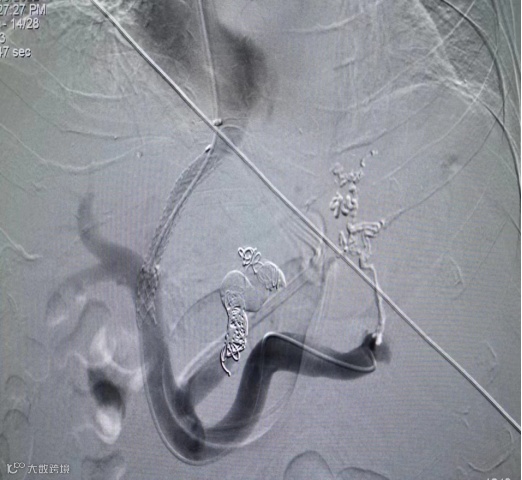

由于李爷爷身体各项指标不符合手术要求,经一段时间治疗后,医生为李爷爷行Tips(经颈静脉肝内门体分流术)。

术后复查依然采用可分离式牵线磁控胶囊胃镜,结果显示李爷爷术后恢复良好。